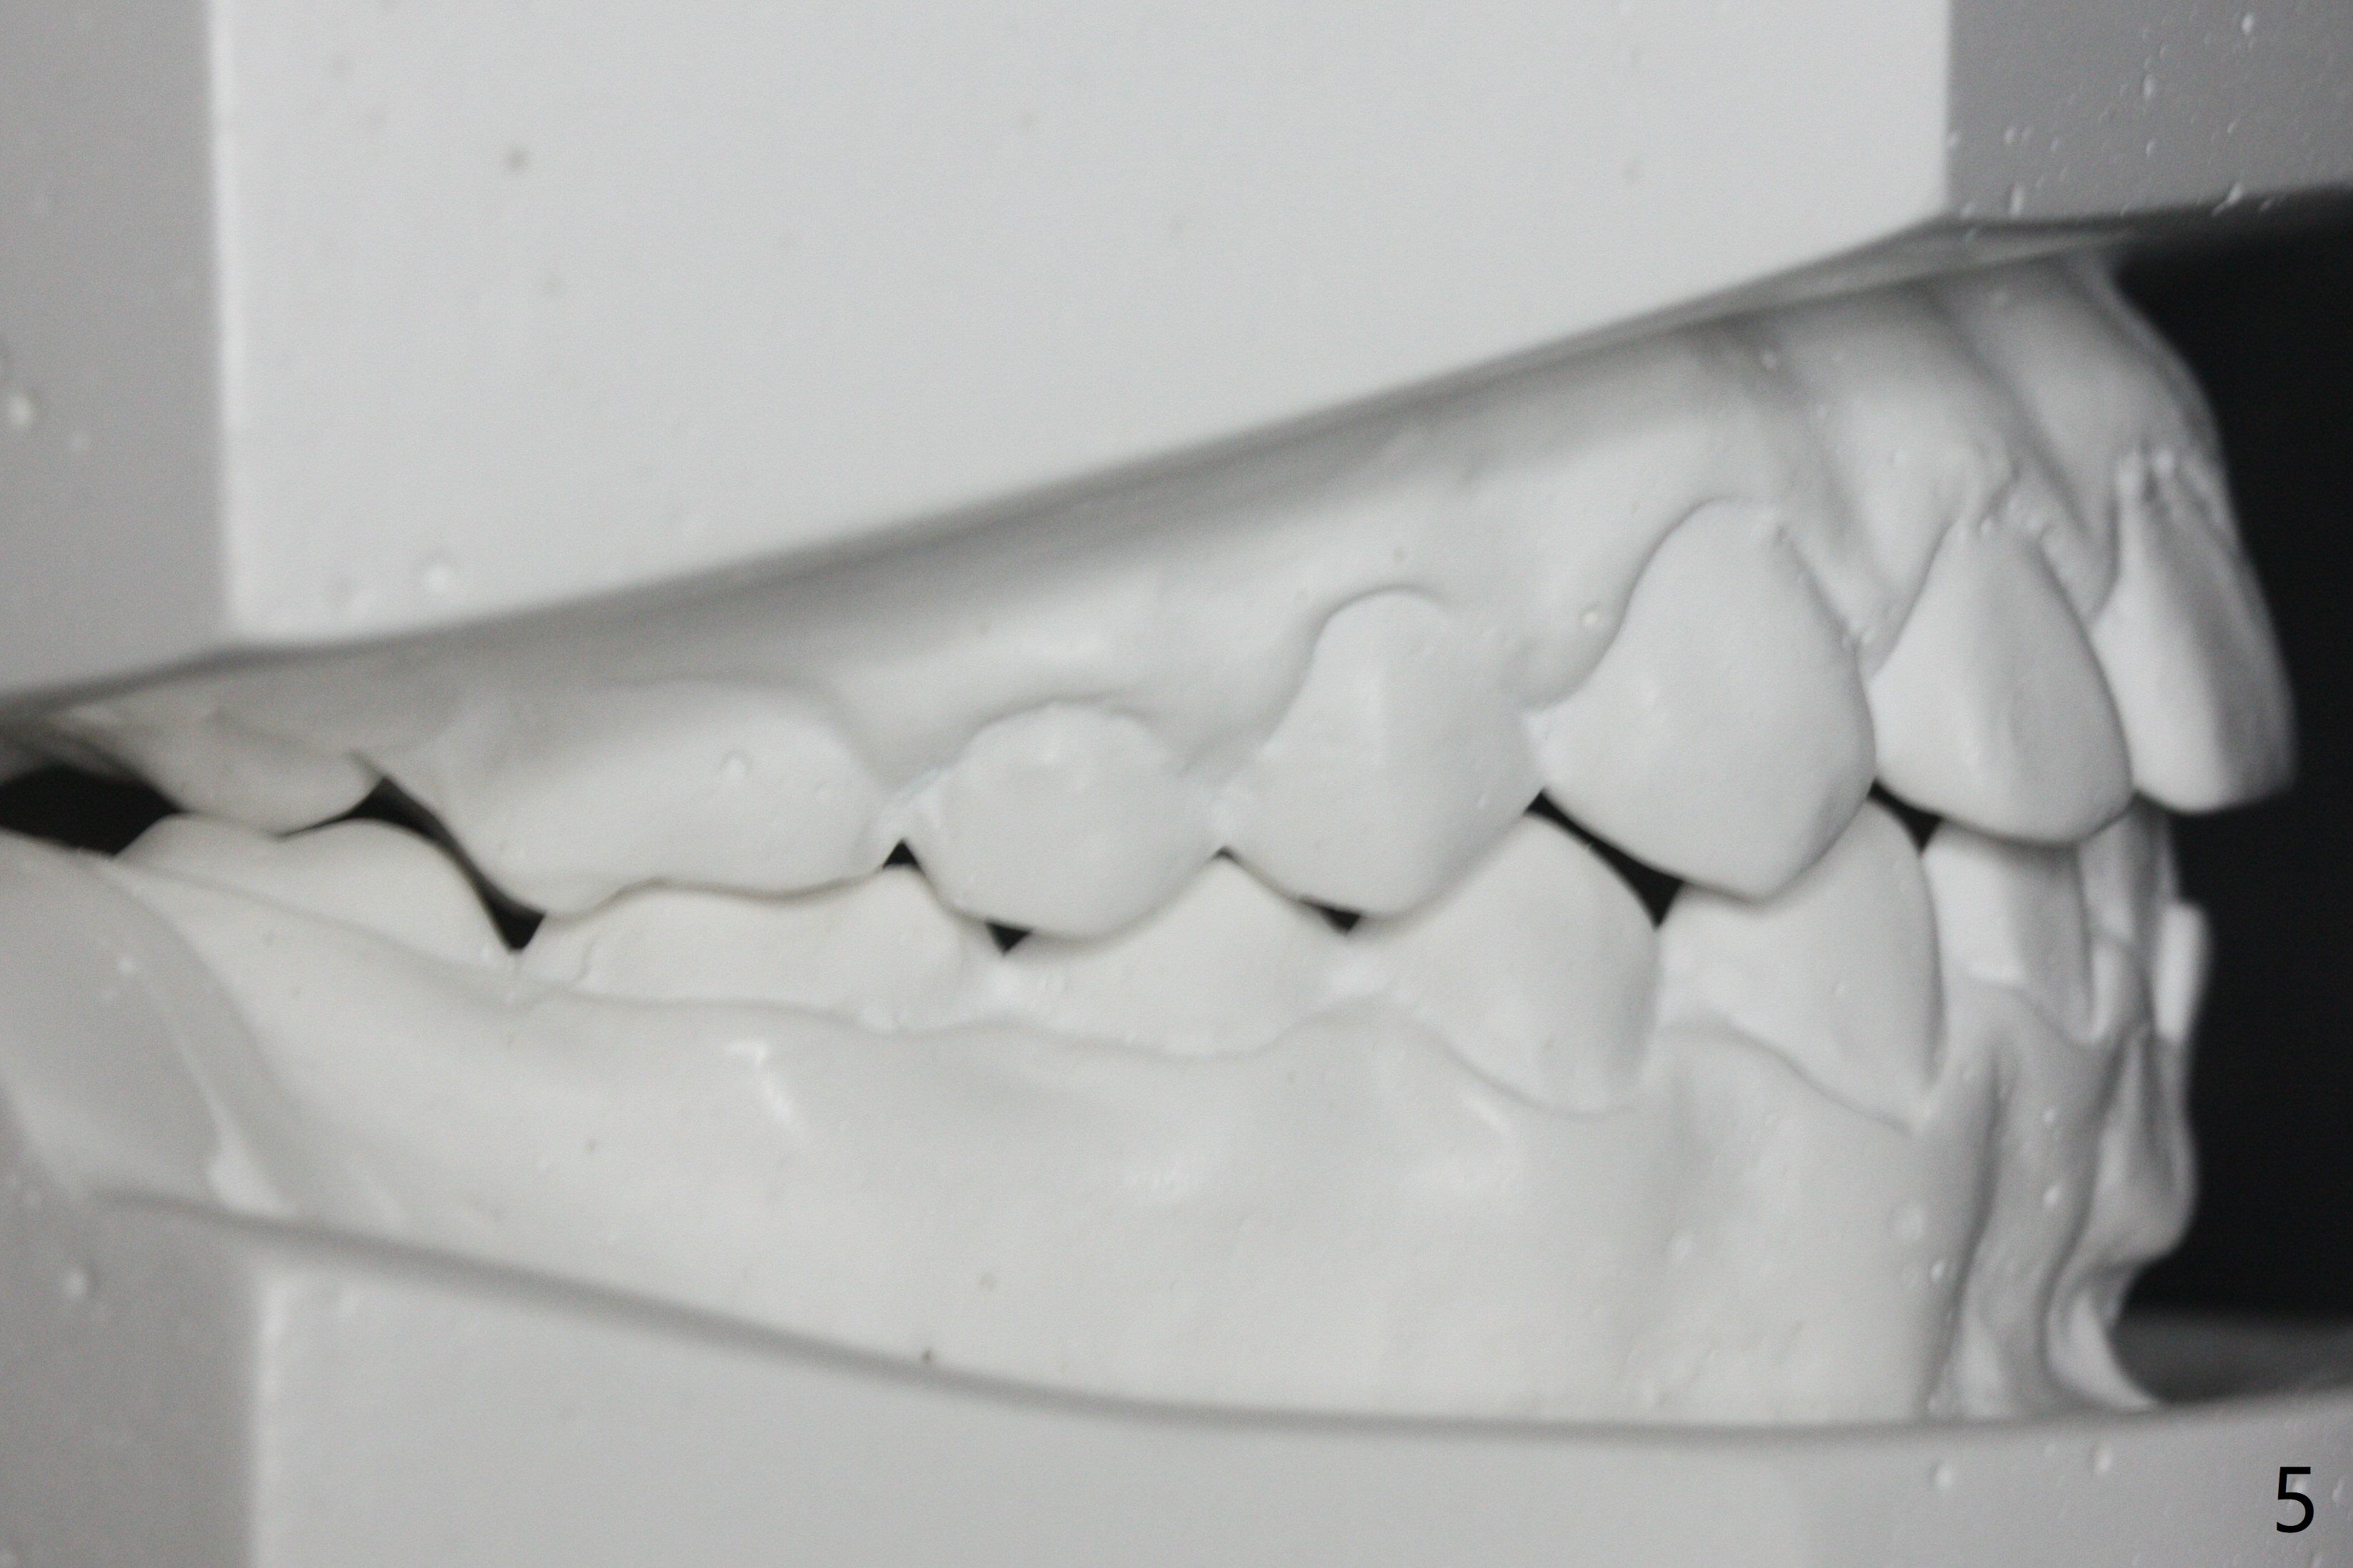

A 11-year-old man starts orthodontic treatment and finishes in 9 months. Two years later crowding relapses because of loss of suck down retainers. It appears that lingual retainer is necessary.